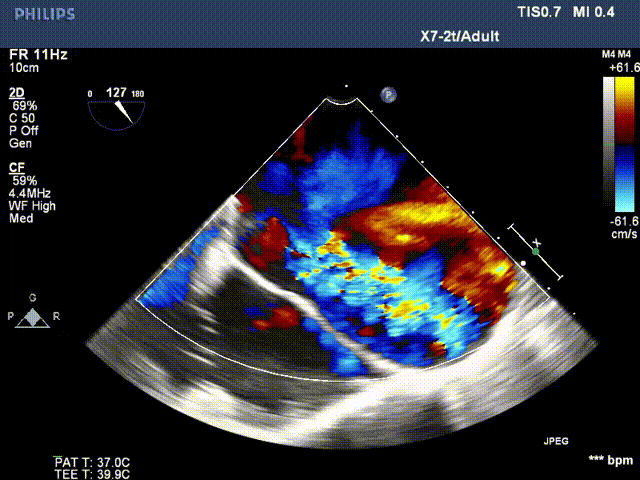

超声检查

患者二尖瓣机械瓣瓣周可见两处间隙,分别位于10点位、1-2点位,大小分别约为:10点位7×5mm,1-2点位10×4mm,彩色血流提示二尖瓣位瓣周返流(两束,大量),主动脉瓣位机械瓣上血流速度正常,瓣周未见明显返流。

心脏超声可见两处二尖瓣瓣周漏